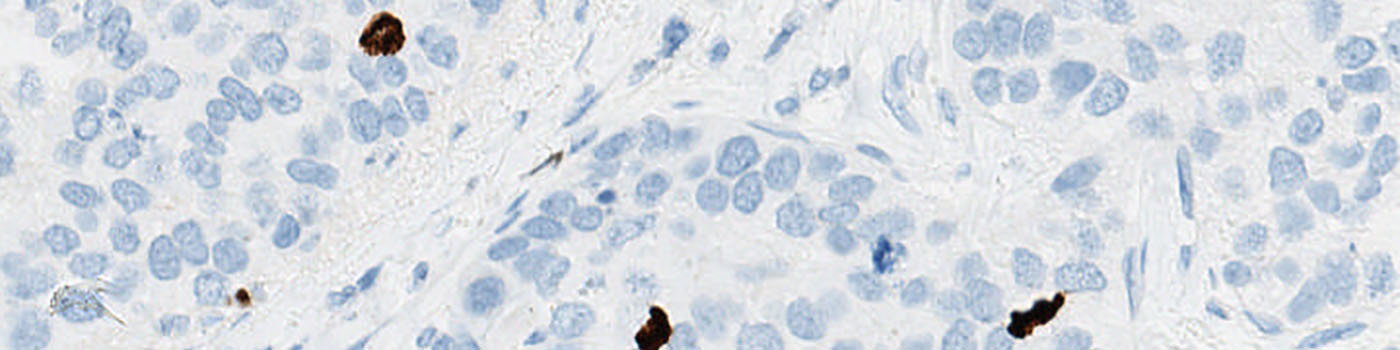

Original TMA-core stained with PCK.

Two serial sections stained respectively for PHH3 and Pancytokeratin (PCK) must be used in this APP. Tumor regions are identified automatically on the PCK stained slide and the outlined tumor region is overlaid on the PHH3 stained slide, thus automatically identifying tumor regions.

PCK is used as a cytoplasmatic marker to localize the cancer tissue.

To employ the VDS approach for PHH3, two serial sections must be stained for PHH3 and PCK respectively.